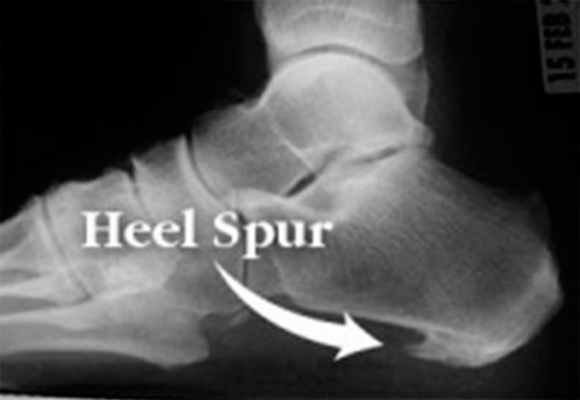

Пяточная шпора представляет собой остеофит пяточной кости. Этиологией шпор является наследственность, нарушения обмена веществ, туберкулез, ревматоидный артрит и системные воспалительные заболевания. К буграм пяточной кости прикрепляется множество мышц и подошвенная фасция, которые оказывают тракционное усилие на кость. Если пяточная шпора располагается на задней поверхности пяточной кости, то это дорсальная пяточная шпора, если она находится по подошвенной поверхности, то это подошвенная пяточная шпора. Дорсальные шпоры часто ассоциируются с тендинопатией ахиллова сухожилия, в то время как подошвенная шпора связана с подошвенным фасциитом. Вершина шпоры находится либо в месте прикрепления фасции на медиальном бугорке пяточной кости, либо в месте прикрепления мышцы короткого сгибателя пальца. Подошвенная фасция во время ходьбы претерпевает постоянное растяжение в связи с ритмичным опусканием и подъемом свода стопы, что приводит к хроническому растяжению апоневроза, которое предрасполагает к воспалительной реакции. Пронация стопы вызывает асимметричное натяжение подошвенной фасции. Избыточная пронация приводит к увеличению натяжения подошвенного апоневроза в месте прикрепления к бугру пяточной кости и считается основным механическим фактором развития подошвенной пяточной шпоры. Хроническая микротравма, которая вызывает разрывы подошвенной фасции вблизи ее прикрепления к кости, приводит к воспалению с дальнейшим развитием оссификации. Пяточная шпора прогрессирует в связи с длительным давлением на подошвенную фасцию и мышцы стопы, или растяжением подошвенной фасции вследствие избыточной подвижности 1 луча. Гиперподвижность структур медиального края стопы дает неравномерность натяжения подошвенной фасции. В области прикрепления фасции к пяточному бугру развивается хроническая микротравма и очаг воспаления, что приводит к развитию фасциита. По мере того, как воспалительный процесс приобретает черты хронического, развивается фиброз и оссификация в области пяточного бугра. Пяточная шпора может протекать либо бессимптомно, либо вызывать боль. Бессимптомные пяточные шпоры встречаются среди нормального взрослого населения в 11% случаев. Большинство пациентов с болью в пятке- это взрослые среднего возраста. У человека под пяткой появляется болезненный участок. Боль, которая локализуется в области медиального бугорка пяточной кости, вызвана давлением на подошву стопы в области прикрепления подошвенного апоневроза к пяточной кости.

Рис. 7. Рентгенограмма стоп. Пяточная шпора